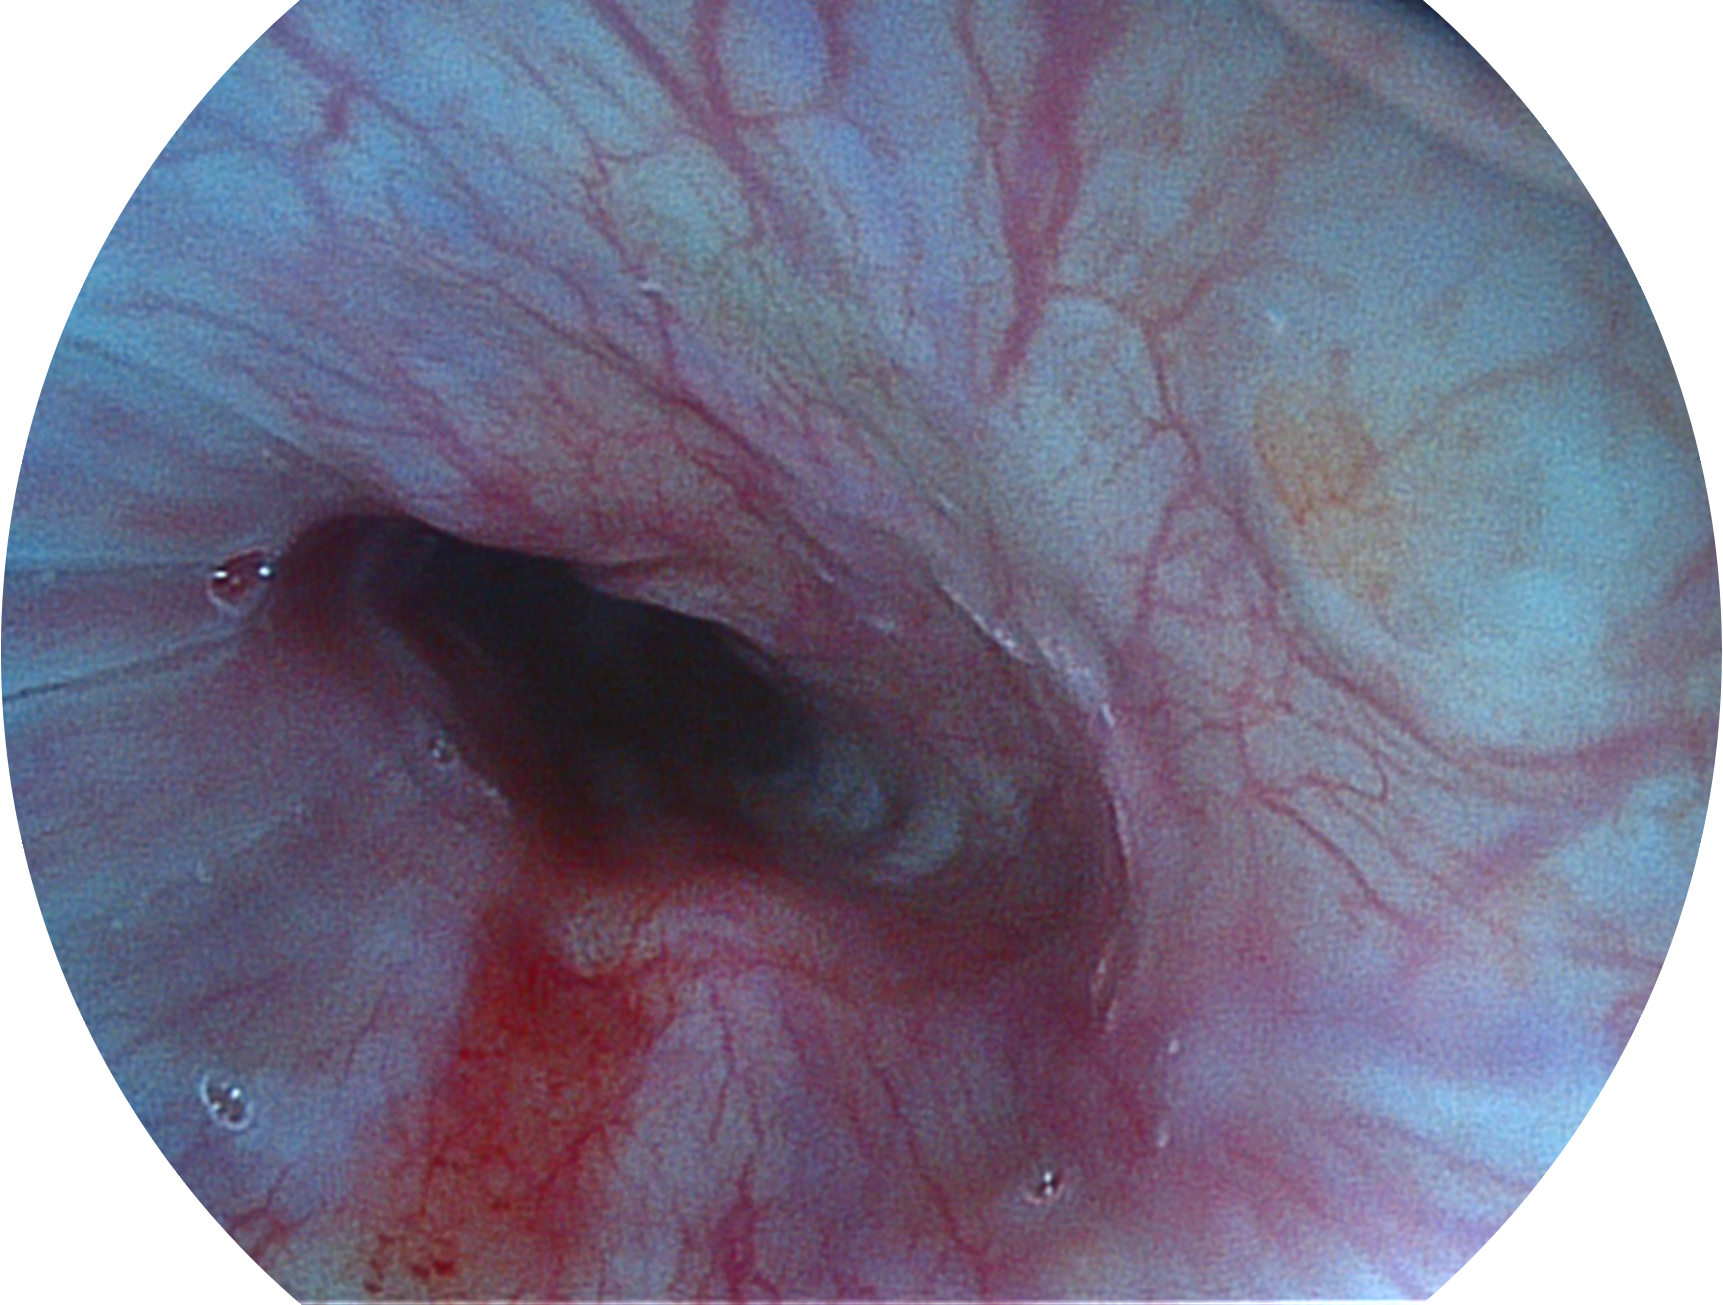

银河集团官网新开发的内镜染色技术,主要是基于多波长LED 光源的开发,VLS-55Q 四波长LED 光源是由四个不同颜色的LED光按照相应照明模式所规定的特定发光比例进行合束后形成,合束后形成的照明光的光谱由红光、绿光、蓝光及蓝紫光这四个不同的波段范围构成。具有更高光谱自由度,通过光谱比例的控制,实现了聚谱成像技术,英文全称为“Spectral Focused Imaging, SFI”,缩写为“SFI”和光电复合染色成像技术,英文全称为“Versatile Intelligent Staining Technology, VIST”,缩写为“VIST”。